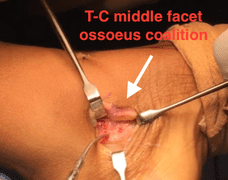

Through his extensive training, Dr. Majdanski has been able to master minimal incision techniques to resect the coalitions.

Pictured above is a middle facet coalition which was resected through a 2cm incision.